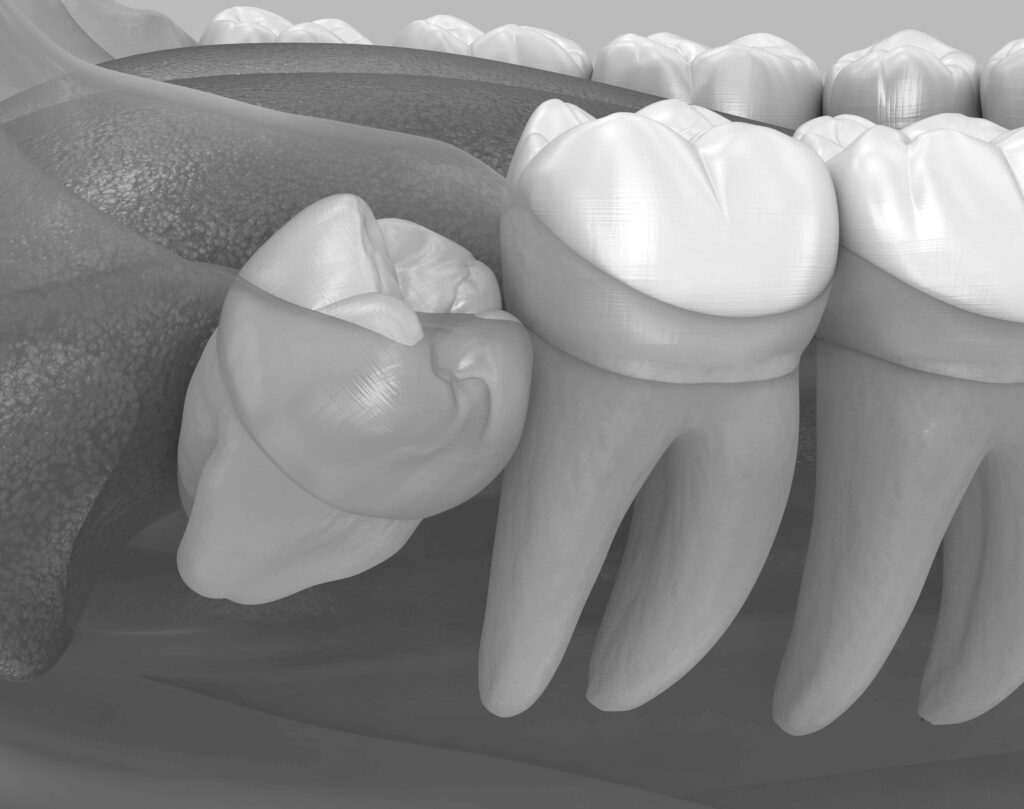

사랑니는 입 안에서 가장 마지막에 나오는 치아로 구강 구조 상 공간 부족으로 인해 정상적인 위치에서 자라기 어려운 경우가 많습니다. 이러한 사랑니는 성장 과정에서 주변 치아를 밀거나 염증을 발생시켜 통증과 불편함을 초래할 수 있습니다.

사랑니가 자라는 원인은 인류의 진화 과정에서 구강 구조의 변화 때문입니다. 과거에는 거친 음식을 많이 저작했기 때문에 턱뼈가 컸지만 현대에는 부드러운 식습관으로 인해 턱뼈 크기가 점차 작아지며 사랑니가 자랄 공간이 부족해졌습니다. 이로 인해 사랑니는 비정상적인 위치로 자라거나 매복되는 경우가 많습니다. 이를 방치할 경우 치주 질환, 인접 치아의 손상 등 다양한 문제가 발생할 수 있어 가급적 조기에 발치하는 것이 좋습니다.

사랑니 발치는 예방적 차원에서도 중요한 의미를 가집니다. 사랑니가 정상적으로 나지 못할 때는 주변 잇몸에 염증을 일으키거나 인접한 치아에 압력을 가해 치아 배열을 흐트러뜨릴 수 있습니다.또한 사랑니의 위치나 방향에 따라 발치 난이도가 크게 달라질 수 있습니다.

사랑니의 발치 방법은 형태에 따라 다릅니다. 일직선으로 정상적으로 자란 경우는 비교적 간단한 발치로 처리할 수 있지만 비정상적인 각도로 누워 있거나 부분적으로만 나와 있는 매복사랑니는 보다 세심한 접근이 필요합니다. 매복사랑니는 주변 신경과의 거리에 따라 발치 시 주의가 필요하며 3D CT 촬영은 이를 세밀하게 확인할 수 있는 중요한 검사 장비입니다.